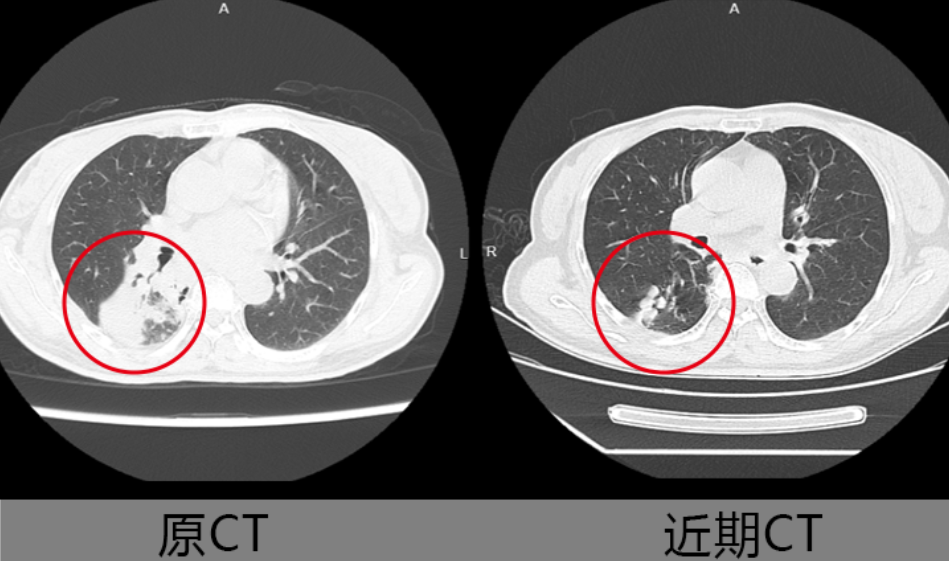

近日,64岁的沈奶奶(化名)因持续咳嗽咳痰一周就诊于绍兴袍江医院。这位有多年肺部炎症史的患者,胸部CT显示右肺炎性病变。王尔东副主任医师团队对比其5年前及近期CT影像,发现右下背段多发实性病灶吸收不佳,不排除结核或阻塞性肺炎可能,建议行支气管镜检查明确病因。